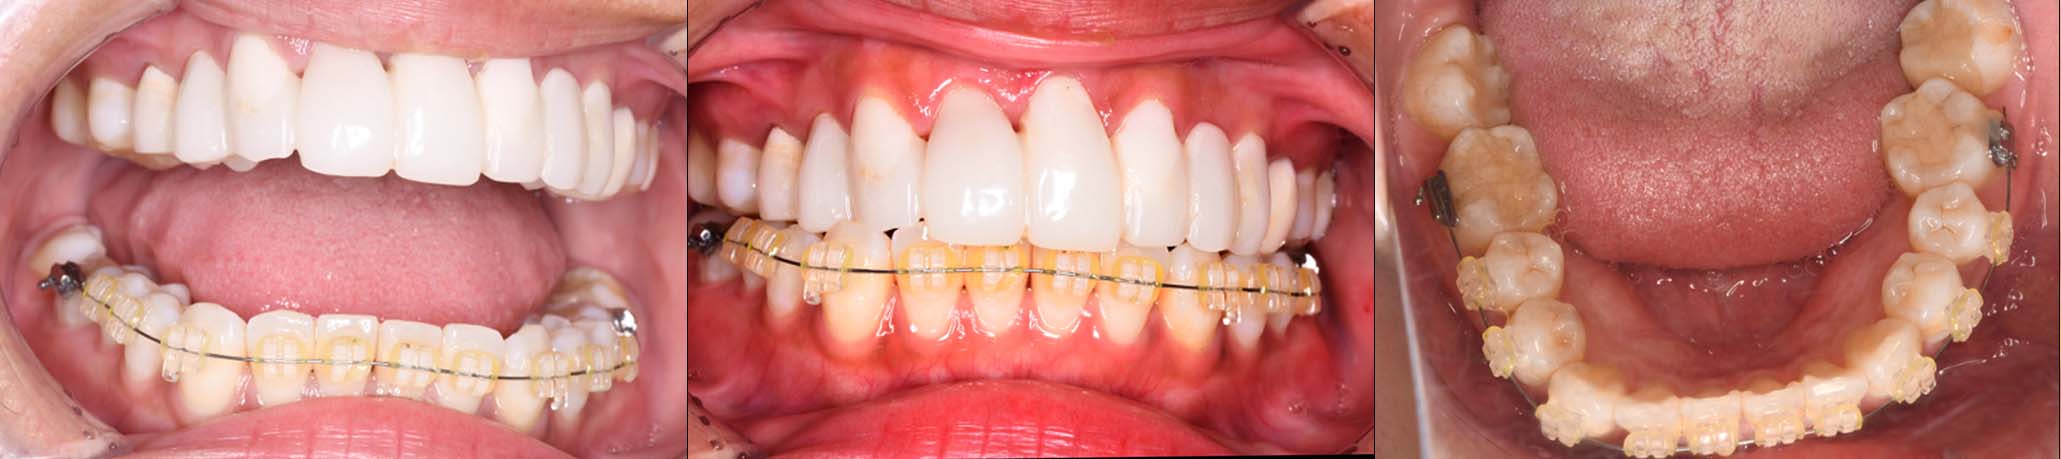

2024年 10月 下顎MTM開始

2024年 10月10日

10月21日

11月7日

11月28日

12月16日

12月23日

1月9日

1月30日

2月20日

3月13日

4月24日

9月25日